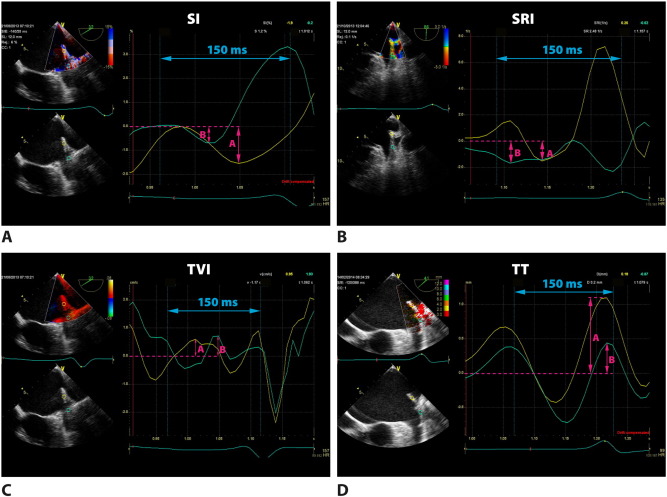

Fig. 4

Fig. 4.

Q-analysis in patient with sinus rhythm (SR). A sample of measurements (arrows) in the area of left lateral ridge in region A (yellow curves) and in region B (green curves). Panel A: strain imaging (SI). Panel B: strain rate imaging (SRI). Panel C: tissue velocity imaging (TVI). Panel D: tissue tracking (TT).

Off-line analysis was performed with the Q-Analysis software (General Electric EchoPac workstation, version 112; upgrade BT12). The TDI recording at 150 ms before the QRS complex was selected for analysis of the systolic phase in all segments. In TEE in the view enabling visualization of the LAA in the longitudinal axis the TDI sector width was selected that included LLR or BMAS. In patients in SR a fragment of the wave at least at 800–900 ms between the QRS complexes before was chosen for analysis. In patients with AF, due to the lack of P wave the TDI sector width was selected in the same period between QRS complexes. Then we analyzed average tissue velocity imaging (TVI), strain imaging (SI), strain rate imaging (SRI) and deformation (tissue tracking, TT) in each area A, B and C in all patients. Atrial systolic parameters could be measured in the late diastolic phase of the mechanical ventricular cycle. Therefore such systolic strain reflecting the extent of myocardial fiber shortening was evaluated as the lowest value below the baseline. For correct presentation the tracking start was placed at the top of the P wave, whereas the tracking end immediately after the QRS complex. Similarly, in SRI we analyzed the lowest value at 150 ms before the QRS complex. The last parameter to measure was deformation TT, showing the highest deflection of the curve at the same time interval. Then we compared peak values obtained in PW-TDI as well as TVI, SI, SRI and TT measured at A, B and C in groups with SR and AF. In patients with AF those with and without LAA thrombus were analyzed separately. Fig. 4 ;  Fig. 5 show an example of measurements at A, B and C in patients in SR and AF, respectively. Differences in TVI, SI, SRI and TT between A, B and C in patients in SR and AF were then submitted for statistical analysis. Additional analyses of subgroups with and without thrombus in LAA were also made.